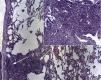

Spontaneous pneumothorax (SP) associated with marijuana or cocaine use is uncommon but not unknown. Although it can be difficult to demonstrate a direct effect, lung damage caused by drug use can predispose patients to pneumothorax.1 We report the case of a 39-year-old man, referred to our unit for treatment of right SP. He had already had SP in the same side 7 months previously and had admitted to occasional use of cocaine. Mechanical pleurodesis was performed via thoracoscopy with resection of the apex of the right lung. Pathology laboratory analysis showed unexpected evidence of non-necrotizing granulomas in the bronchial walls, associated with small vesicles (Fig. 1). The patient had no significant clinical history and all standard clinical laboratory test results, including mycobacteria, fungal infection and human immunodeficiency virus, were negative.

Respiratory tract deposits of particles of talc contained in cocaine were thought to have led to the formation of granulomas as a reaction to a foreign substance. Granuloma growth affected the small airways, causing air retention and bullous disease. Severe cough and bronchospasm caused by the inhalation of cocaine caused increased intra-alveolar pressure, followed by vesicle rupture and pneumothorax.